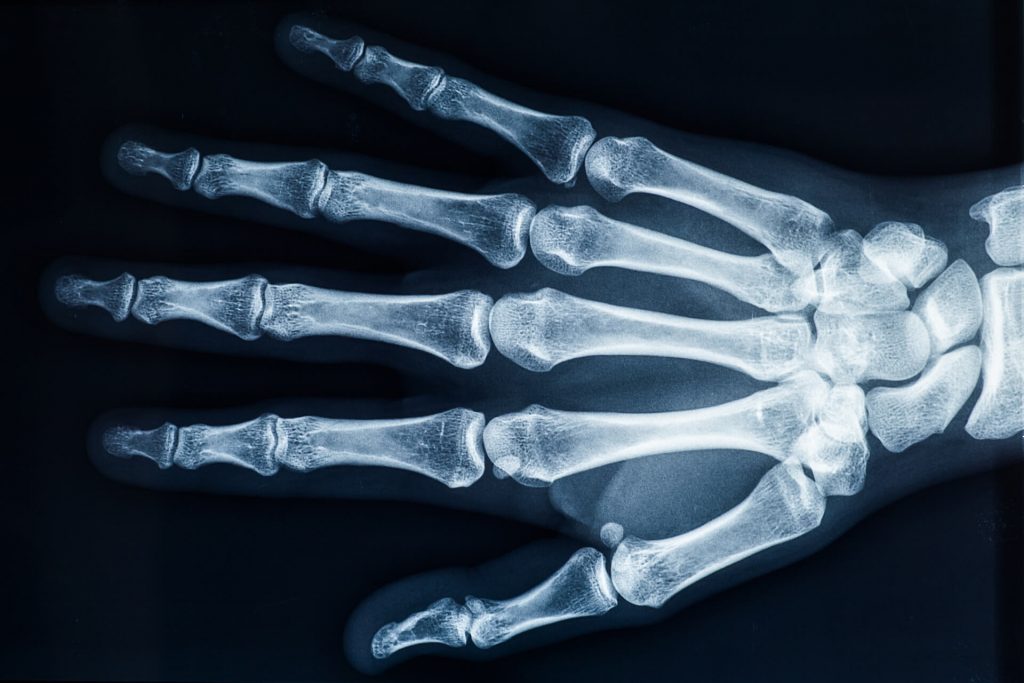

IMAGING

Suggest X-ray

Finger arthritis is an inflammatory disorder that can occur in many different ways. It can be systemic where your body will attack itself in the case of Rheumatoid Arthritis (RA) or it may occur as a result of wear and tear, Osteo Arthritis (OA). While both of these conditions are painful and involve swelling and the de generation of the cartilage insie the joints of the finger, their cause is very different. At Action Rehab Hand Therapy Clinic our Hand Therapists assess and treat a majority of patients who suffer from Osteo Arthritis (wear and tear of the joints) which often occurs as a result of a sporting or repetitive job or task such as gardening. This type of arthritis is very common and can be easily treated. Finger arthritis is painful and it is debilitating and can cause deformities if left untreated. At Action Rehab Hand Therapy Clinic our Hand Therapists, Physiotherapists and Occupational Therapists are experienced in reading x-rays and assessing your hand for arthritis and joint degeneration.